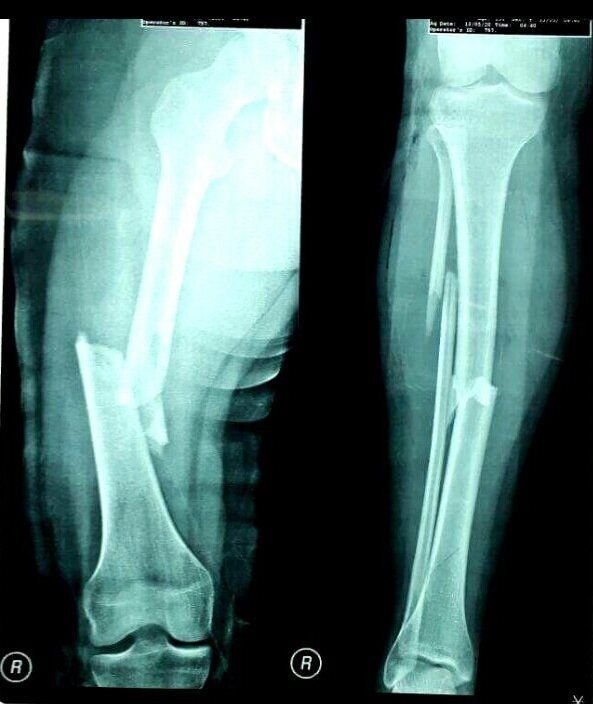

1000853718.jpg

Clinical Trials

Clinical trials on a good number of patients so far have shown no safety concerns. This confirms the glue's efficacy for fixing fractures including complex and comminuted (where bones shatter into many pieces) fractures.

The best part is that it is a minimally invasive procedure that requires only a small incision, leading to a shorter recovery time, reduction of infection and other complications associated with traditional orthopedic surgery.